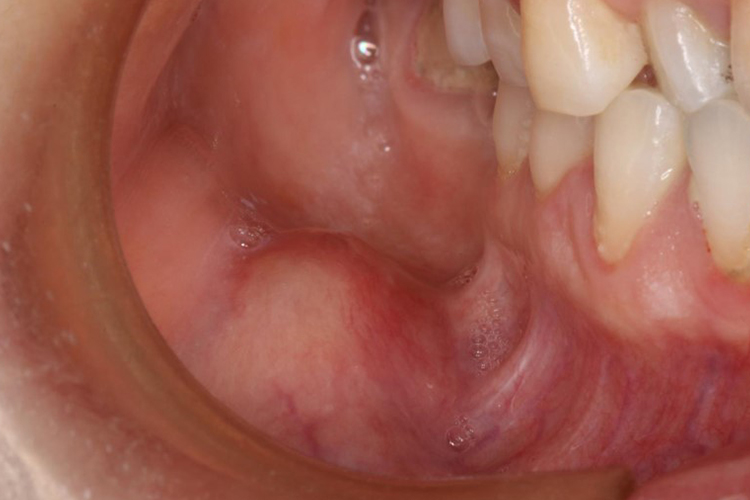

颊黏膜癌病损早期通常有溃疡形成,出现颊黏膜溃烂,可向深部浸润,出现口内增生突起,但无明显张口受限。